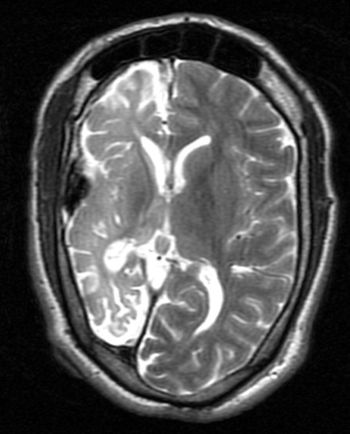

This case is a 26-year-old female in whom MRI imaging was done24 hours after an attempted hanging episode.